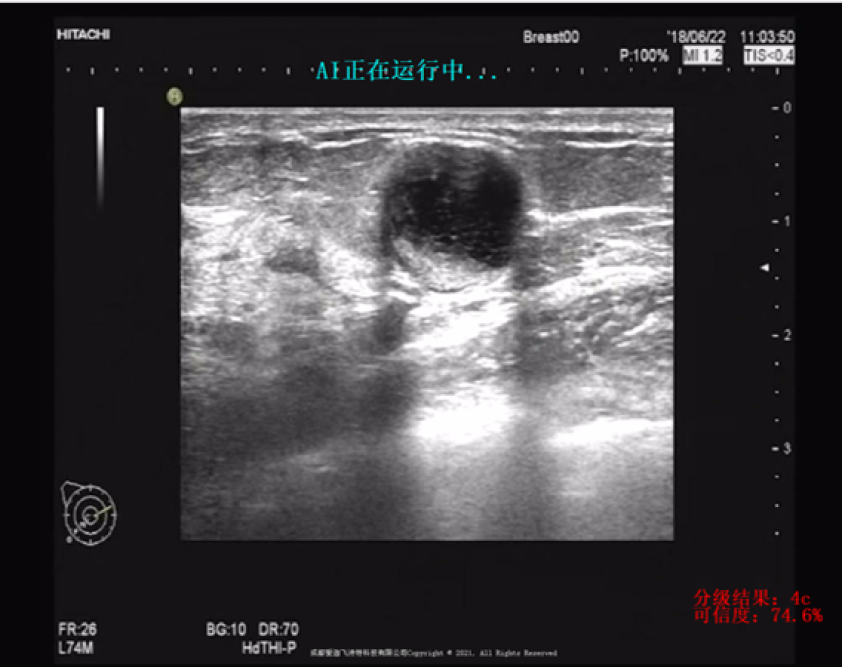

公司占有两院院士在内的10余位技术和产业专家作为照拂,先后与四川大学华西医院等20多家三甲医院成立深度合作关系,打造了智能乳腺系统、智能肺系统、智能远程诊断系统、智能心电诊断系统、智能医学科研平台、智能核医学系统、智能医学影像勾画系统、智能口腔系统、智能骨科系统、智能消化系统共12大产品系统,研发出10余项智能医学系列软硬件产品,推广至全国近200家医院。